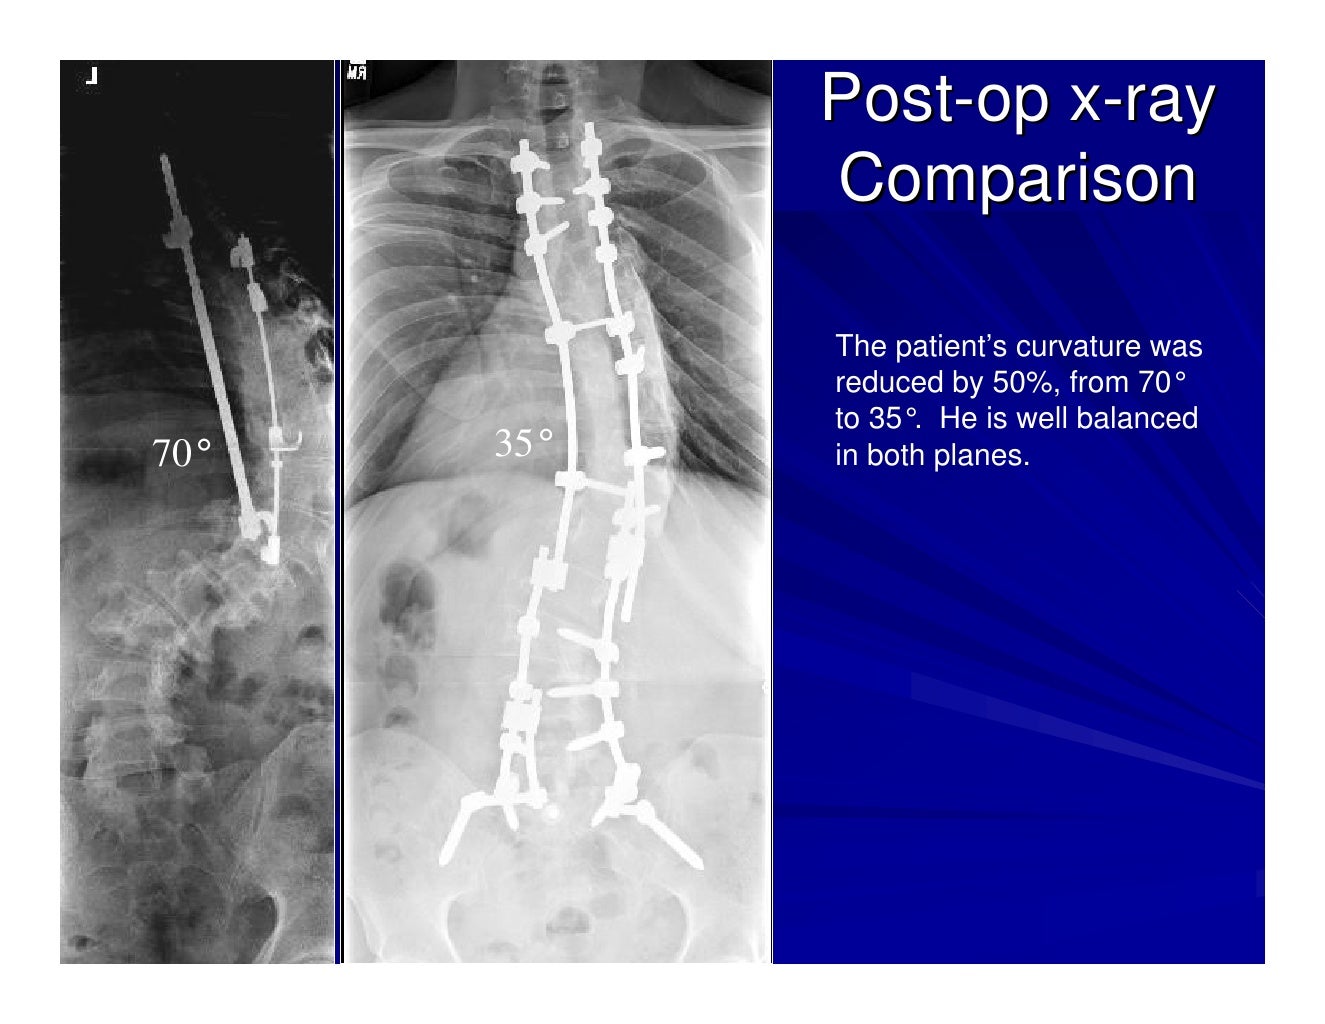

Case Review 1 42 year old make with Adult Scoliosis Harrington Rod Harrington Rods Removal It's attached to the spine with the goal of holding it in a straighter position so its vertebrae can't become more tilted over time. Once the rod is removed,. Scoliosis spinal fusion surgery is performed by inserting a harrington rod with a ratcheting system along the concave part of the curve and attaching it to the spine with two hooks. Harrington Rods Removal.

Case Review 1 42 year old make with Adult Scoliosis Harrington Rod Harrington Rods Removal Harrington rods can bend, break loose from the wires, or worse, break completely in two, necessitating further surgical intervention and removal of the rod. Once the rod is removed,. A wide array of hardware is commonly used in instrumented spinal surgery. It's attached to the spine with the goal of holding it in a straighter position so its vertebrae can't. Harrington Rods Removal.

Case Review 1 42 year old make with Adult Scoliosis Harrington Rod Harrington Rods Removal It's attached to the spine with the goal of holding it in a straighter position so its vertebrae can't become more tilted over time. A wide array of hardware is commonly used in instrumented spinal surgery. A harrington rod for scoliosis is instrumentation used in spinal fusion; Harrington rods can bend, break loose from the wires, or worse, break completely. Harrington Rods Removal.

Case Review 1 42 year old make with Adult Scoliosis Harrington Rod Harrington Rods Removal A wide array of hardware is commonly used in instrumented spinal surgery. Once the rod is removed,. A harrington rod for scoliosis is instrumentation used in spinal fusion; This information is for patients who have had surgical correction of. Scoliosis spinal fusion surgery is performed by inserting a harrington rod with a ratcheting system along the concave part of the. Harrington Rods Removal.

Case Review 1 42 year old make with Adult Scoliosis Harrington Rod Harrington Rods Removal This information is for patients who have had surgical correction of. A harrington rod for scoliosis is instrumentation used in spinal fusion; It's attached to the spine with the goal of holding it in a straighter position so its vertebrae can't become more tilted over time. A wide array of hardware is commonly used in instrumented spinal surgery. Scoliosis spinal. Harrington Rods Removal.